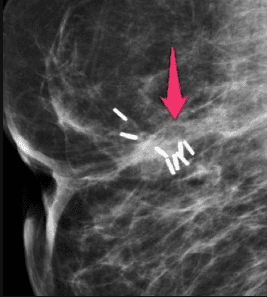

Hình ảnh sẹo vú sau phẫu thuật thường biểu hiện với vùng rối loạn cấu trúc, khối mô mềm bờ không rõ xen kẽ với những vùng thấu quang hoặc biểu hiện với khối bờ tua gai, đôi khi khối có nhiều nốt vôi hóa kèm theo. Sẹo vú sau phẫu thuật thường liên quan với sẹo trên da hoặc vùng can thiệp ngoại khoa trước đó. Chụp nhũ ảnh giúp đánh giá sẹo vú tốt hơn khi được đè ép và phóng đại tổn thương, đặc biệt với vật liệu định vị (kim định vị, dây định vị), nhũ ảnh có thể giúp phân biệt sẹo vú sau phẫu thuật với tổn thương khối ác tính khác. Tổn thương này sẽ ổn định hoặc giảm kích thước dần theo thời gian khi so sánh trên các phim nhũ ảnh.

Hình 1: Nhũ ảnh có hình ảnh co rút mô vú sau phẫu thuật và xạ trị.